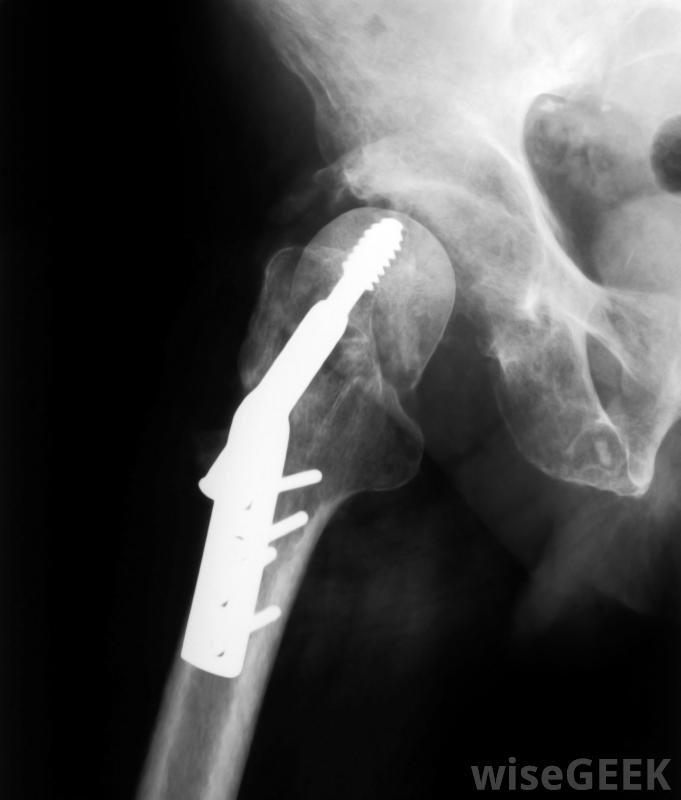

治療上,抗重力跑步機可以讓患者更快地移動,通過減輕患者受傷或新修復的關節、膝蓋或臀部的重量,在康復過程中更早地建立肌肉張力。抗重力跑步機的應用還包括肌肉或腿部損傷,以及老年人的康復。

髖關節手術或髖關節手術后通常建議使用抗重力跑步機更換。